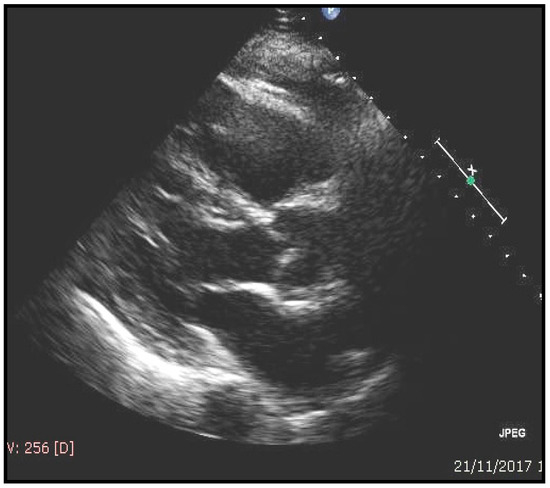

| ECHOCARDIOGRAFIC evaluation | Value | normal range |

| Septal thickness, mm | 13.8 | 0.6–0.9 |

| Posterior wall thickness, mm | 12.9 | 0.6–0.9 |

| LV end-diastolic diameter, mm | 45.5 | 39–53 |

| LV mass/Body surface area, g/m2 | 120.4 | 44–88 |

| E/e1 | 13 | <10 |

| Ejection fraction (%) | 49.5 | ≥55 |

| Atrial volume/Body surface area, mL/m2 | 46.4 | 16–28 |